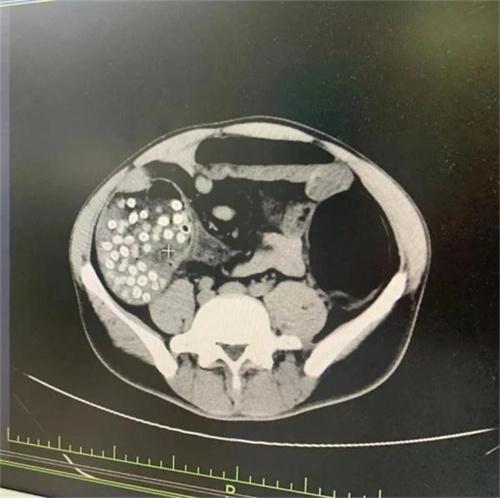

隨著年齡的增長,老人在腸道功能方面本來就會更弱一些,尤其是因為直腸癌或者腸道曾經受損,做過手術的一些人群,不吐核并且把楊梅核咽下,很容易讓腸梗阻出現。其中有一個52歲的田伯,因為吞下的楊梅核太多,將腸道已經結實的堵住了,這是因為其還有另一大重要的原因——有腸道腫瘤。這使得腸腔變得很狹窄,吞下大量楊梅核后,無法自行將這些楊梅核排出來,情況極為危急,拖下去很可能有生命危險,必須馬上做出手術。